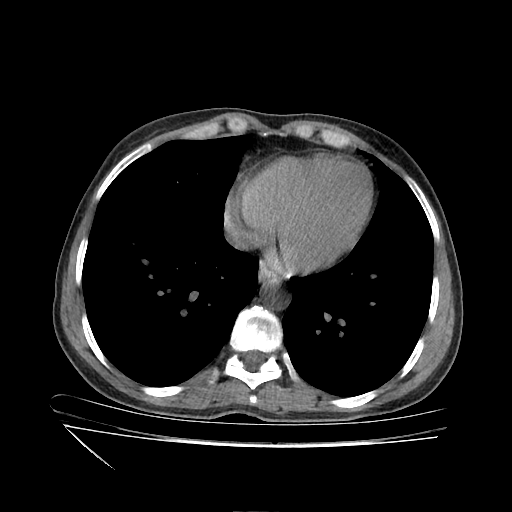

Original NATIVE CT scan (input)

No window - Raw intensity values

Reconstructed NATIVE CT scan (cycle consistency)

Original VENOUS CT scan

Generated VENOUS CT scan (A→B translation)